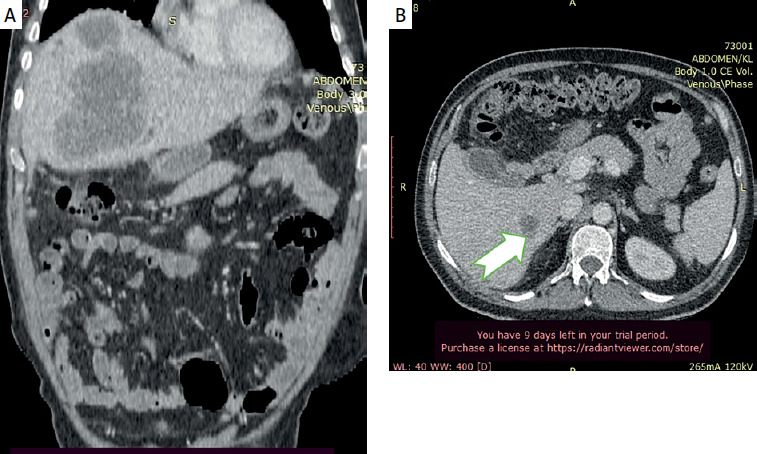

Primary squamous cell carcinoma of the liver.